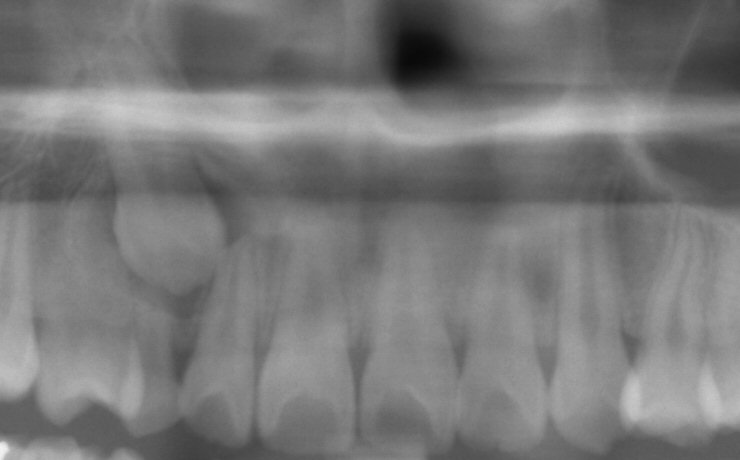

Fig. 13 Initial panoramic radiograph (cropped) of impacted lower left canine (at 16 y.o.)

© Copyright 2007-2014, Vu Orthodontics. All rights reserved.